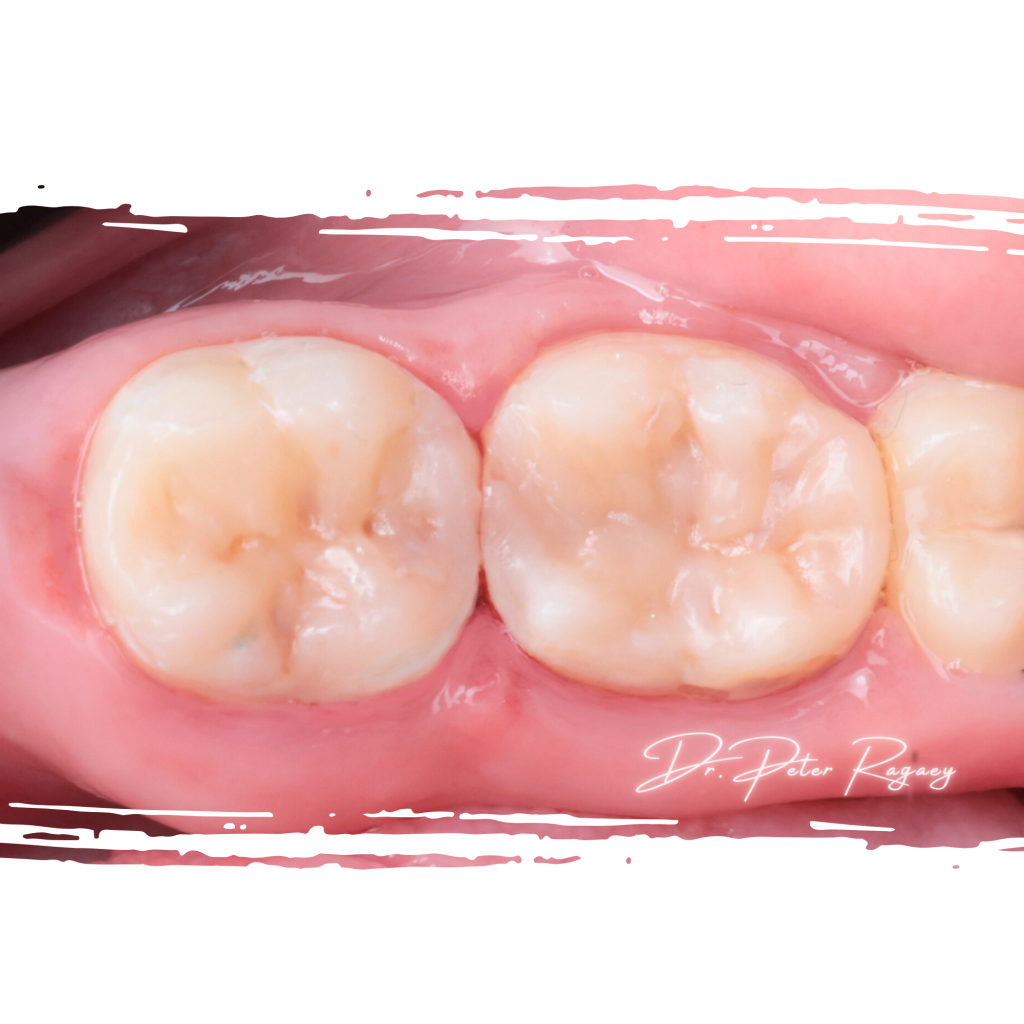

Case presentation: A 25 year old female patient presented to our restorative department

Patient’s chief complain was pain in the lower right posterior area, after clinical and radiographic examination the following was diagnosed:

Deeply carious LR 6 and 7 with enamel

7. Full cavity and morphological reconstruction was completed Using G-aenial universal injectable composite following the cusp by cusp technique, restoring all the anatomical details of the occlusal surface.

9. Final finishing and polishing using twist wheels and Polishing paste